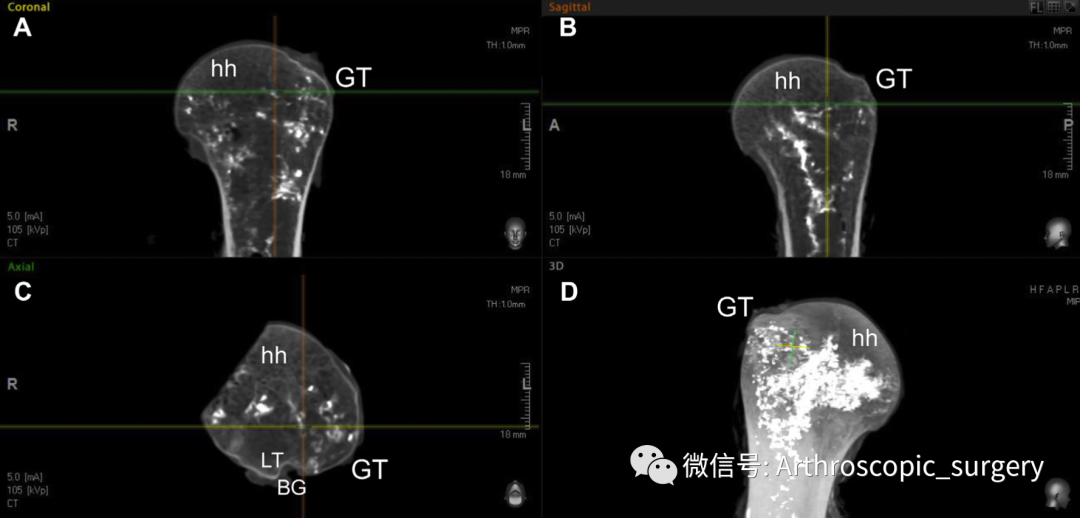

而通过微聚焦CT扫描可以发现肱骨头内血供的分布大致情况,大结节处血供相较而言比较差。肱骨头(hh);高风险区(the high-risk zone,hrz);肱骨大结节(GT)